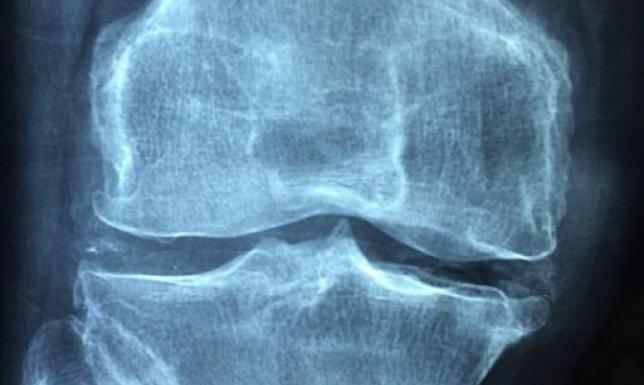

Miasto Suwałki wraz z Akademią Fundacja Aktywnego Rozwoju zaprasza mieszkańców Suwałk w wieku 30+ na bezpłatne badania densytometryczne osteoporozy oraz bezpłatne badanie słuchu.

Każda diagnozowana osoba otrzyma wynik wraz z informacją o stanie swojego układu kostnego. Po wykonanym badaniu możliwa jest konsultacja z lekarzem reumatologiem.